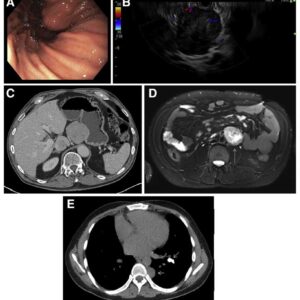

QUIZ: Tumores múltiplos em um paciente jovem

8 de junho de 20236 de junho de 2023

Notícias, Quiz